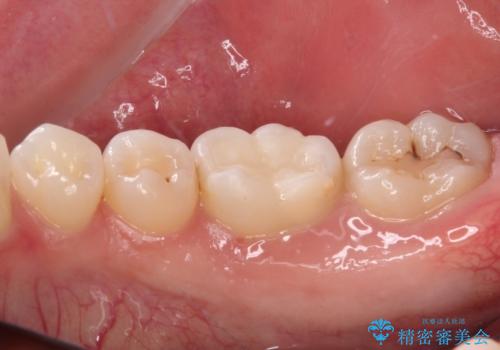

むし歯治療した歯にセラミックを入れたい セラミックインレー修復

- 他院にてむし歯の治療をし、当院にてセラミックを入れたいとのことで来院された患者様です。

むし歯がないか確認し、セラミックインレーにて修復することとしました。

セラミックインレー装着時には、唾液の侵入を防ぐために、ラバーダム防湿を行いました。

見た目、噛み合わせともに満足していただけました。

ラバーダム防湿を行い、セラミックの接着をすることで、唾液や血液などの接着阻害因子を排除することができます。